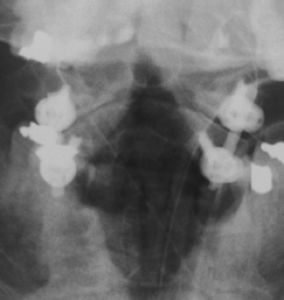

Stabilisierende Operationen

Zeigt sich ein höhergradiger Verschleiß bzw. eine ausgeprägte Instabilität, wird der betroffene Wirbelsäulenabschnitt versteift (Fusion). Kombiniert mit diesem Verfahren kann ggf. auch eine Erweiterung des Wirbelkanals (Dekompression) bei Verengung (Spinalstenose) erfolgen.

Wirbelkörperersatz

Bedingt durch eine Entzündung, einen Bruch oder eine Tumorerkrankung kann ein Wirbelkörper vollständig zerstört werden. Durch einen Platzhalter wird der betroffene Wirbelsäulenabschnitt rekonstruiert und stabilisiert.